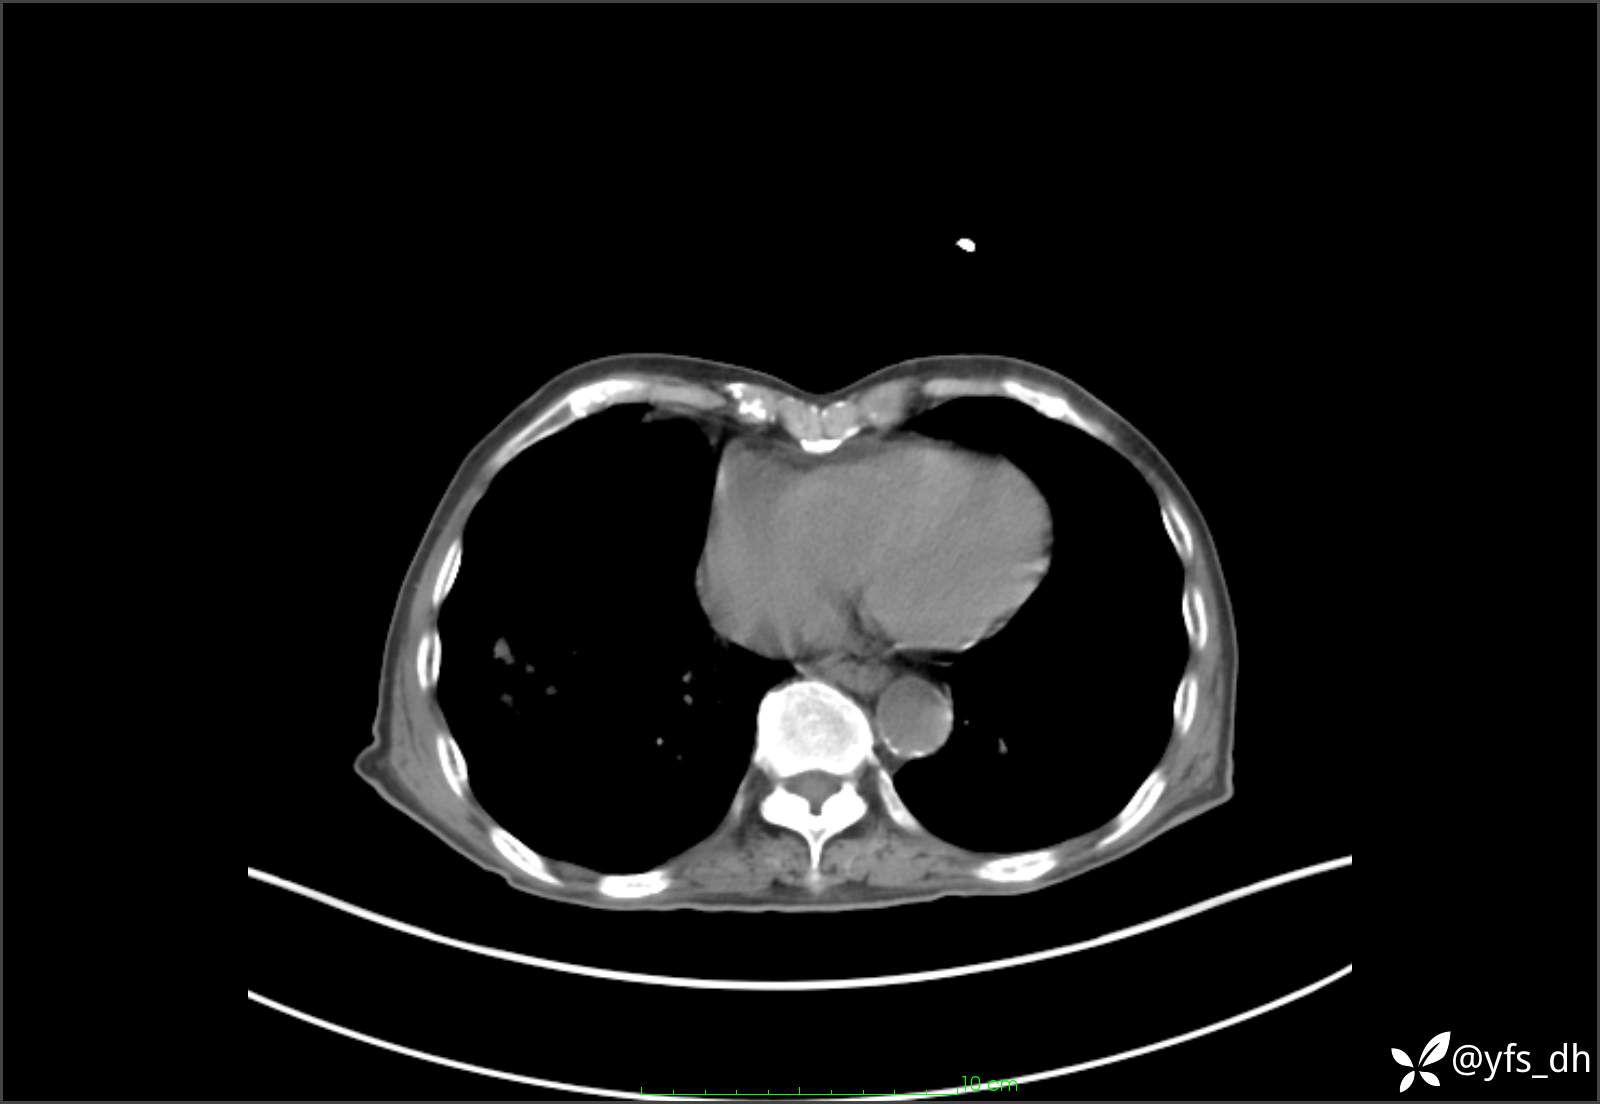

1.简要病史:患者4天前突发上腹部疼痛不适,但可以忍受。3小时前饭后突然加重,不能忍受后就诊。

2.简要手术记录:术中见腹盆腔大量肠液及粪便,乙状结肠中下段见一约3cm的破口。